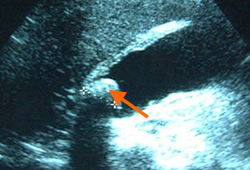

Ultrassonografia de colecistite aguda e presença de cálculos biliares: a seta aponta para um cálculo no fundo da vesícula biliar, com sua sombra ecogênica abaixo

Cortesia de Charles Bellows e W. Scott Helton; usado com permissão